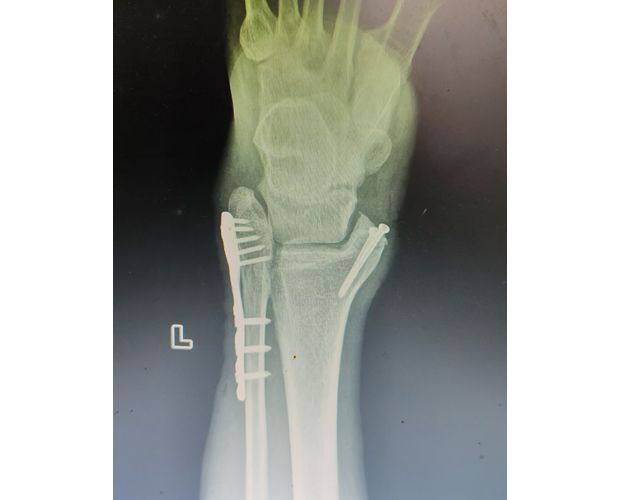

2月4日,何店鎮(zhèn)中心衛(wèi)生院接診一名左踝關(guān)節(jié)外傷患者,經(jīng)影像檢查,確診為左脛、腓骨下段骨折。外科醫(yī)生姜穩(wěn)迅速完成術(shù)前檢查及病情評估,并與患者及家屬深入溝通治療方案。在患者強烈要求于本院進行手術(shù)的情況下,為最大限度保障手術(shù)質(zhì)量與安全,該院特邀請醫(yī)共體牽頭單位——曾都區(qū)人民醫(yī)院脊柱創(chuàng)傷外科專家團隊前來指導(dǎo)。

本次幫扶由曾都區(qū)人民醫(yī)院脊柱創(chuàng)傷神經(jīng)外科主任徐三軍帶隊,專家團隊抵達后立即完成手術(shù)風險評估及術(shù)前準備。手術(shù)過程中,徐三軍主任嚴格規(guī)范完成各項手術(shù)操作,并同步結(jié)合手術(shù)步驟,為該院外科醫(yī)師詳細講解骨折手術(shù)的關(guān)鍵要點、操作技巧、術(shù)中注意事項及術(shù)后康復(fù)要領(lǐng)。通過“手把手”的實戰(zhàn)帶教,專家將豐富的手術(shù)經(jīng)驗與規(guī)范的診療思路傾囊相授,讓該院醫(yī)護人員在實操中學(xué)習(xí),在過程中成長。